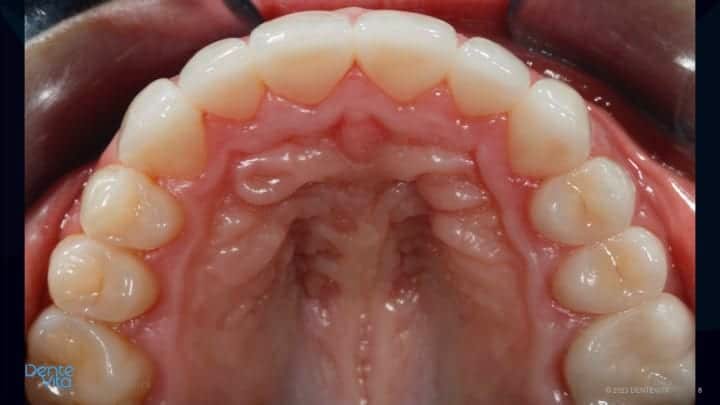

This case study addressed significant tooth erosion from gastric reflux. Lost vertical space from vertical tooth drift was reversed with orthodontic treatment (intrusion and alignment therapy).

After completion of successful orthodontic therapy, missing tooth structure was rehabilitated/restored with conservative 360 degree and three-quarter porcelain veneer therapy, along with posterior occlusal partial coverage onlay restorations.